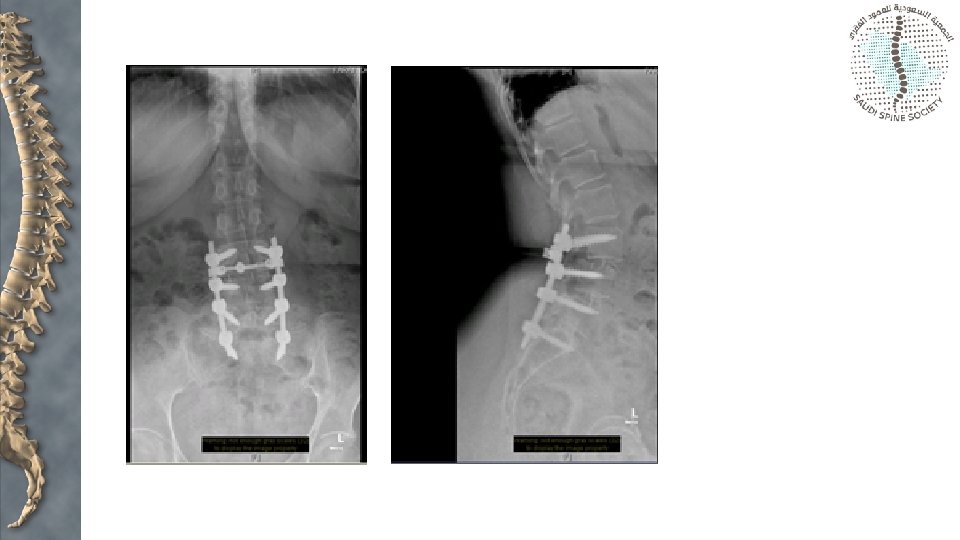

Surgical options • Fusion in situ and decompression • Decompression and reduction • Posterior lateral fusion and anterior column support

Gill laminectomy • Nerve root decompression • Removal of lamina of the affected level • May lead to increased instability • Radicular symptoms may persist unless decompression is accompanied by fusion to stabilize the segment in order to prevent ongoing neural irritation

High grade • Gaines resection • Sacral osteotomy • Fibular strut - Bohlman • Increased risk of neurological compromise (L 5 nerve root) with attempted reduction